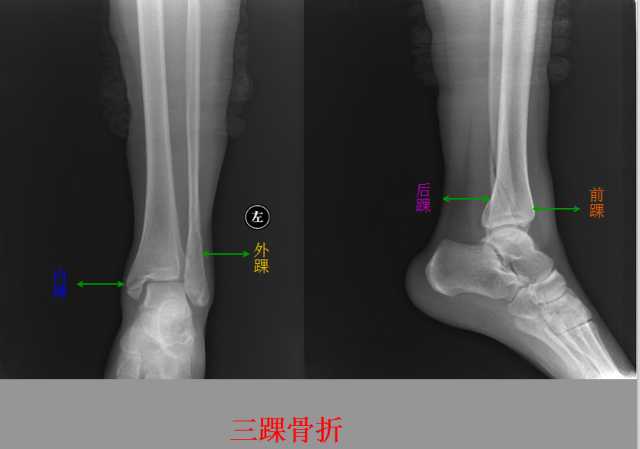

骨折篇

定义:骨折{Fracture}是指骨的完整性和连续性的折裂或粉碎。包括创伤性骨折、疲劳性骨折和病例理性骨折。 临床上以创伤性骨折*常见。